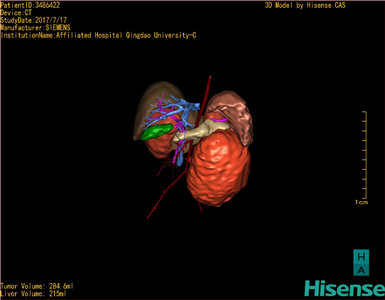

肾母细胞瘤-CH-001-N-001503

CT结果输入海信CAS系统后行3D重建及手术规划后,于2017-7-21全麻下行“左肾切除术”手术治疗:

术前三维重建及手术方案设计:

将0.625mm双源薄层CT资料的静脉期和动脉期Dicom格式文件导入海信CAS系统。

通过调节窗宽窗位调整CT序号,对肿瘤,肝实质,胆囊,下腔静脉,肿瘤,肝动脉、门静脉及肝静脉等进行三维重建;系统自动计算肿瘤体积和肝脏体积。

模拟手术操作,自动计算切除肿瘤体积。肝脏体积为215ml,肾脏肿瘤大小为284.6ml通过术前模拟手术,精准判断手术可行性。

术前三维重建:

重建图片